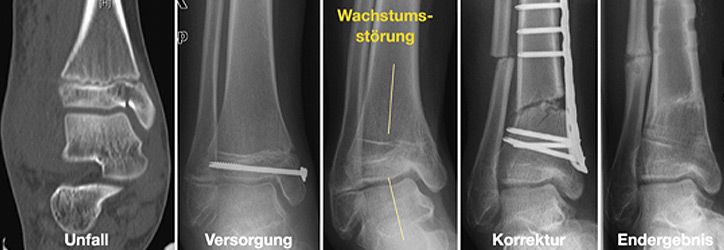

Korrekturoperation

Nur selten treten Wachstumsstörungen oder Verheilungen in Fehlstellung auf. Um dennoch eine volle Belastung und uneingeschränkte Beweglichkeit zu gewährleisten, führen wir entsprechende Korrekturoperationen durch.